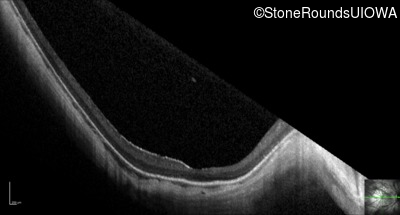

Optical Coherence Tomography - Left - 10/100 -2

Exemplar / OCT Stack